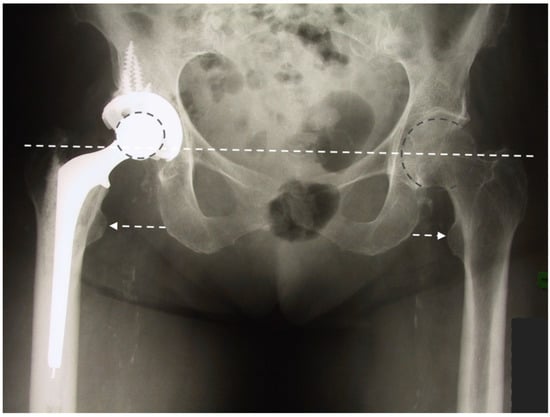

Using a LDH THA allows unrestricted movement after THA for all types of surgical approaches. Vendittoli’s group in Canada practices no postoperative ROM restriction for the posterior surgical approach, as it simplifies patients’ education, enhances their confidence during rehabilitation, and facilitates bilateral procedures [,]. LDH monobloc DM is especially interesting for many older women with large femurs and a small acetabular cavity (<50 mm, Figure 7). In these cases, using a standard bearing diameter is prone to instability. With its LDH, DM design provides optimal implant stability for these not so infrequent patients. Moreover, with LDH, we do not impose activity restrictions in the long term. LDH CoC THA offers a significant benefit for many active individuals who can return to their regular jobs and for those who want to practice demanding sporting activities.

Figure 7.

(a) Antero-posterior pelvis radiograph of a 75-year-old woman with severe bilateral hip osteoarthritis. During the right THA surgery, the acetabular cavity was reamed to 47 mm. A monobloc acetabular component of 48 mm was implanted with a DM polyethylene head of 41 mm (28 mm metal head). A polished tapered stem was cemented. (b) Post-operative anteroposterior pelvis radiograph.